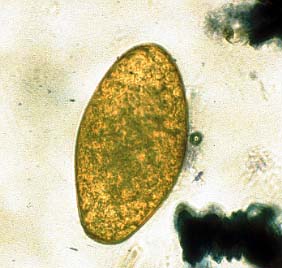

Die Standardmethode für den Nachweis eines Befalls mit F. hepatica am lebenden Tier stellt nach Ablauf der Präpatenzzeit (Rind 56 – 77 Tage, Schaf 55 – 57 Tage) die Koproskopie dar  (s. Abbildung 4). Die Sensitivität beträgt – je nach Vorgehen – zwischen ca. 70 und 90 %. Weitere Untersuchungsmethoden sind der serologische Nachweis von Antikörpern oder Antigen, der Nachweis von Koproantigen oder die Untersuchung von Galle auf Parasiteneier (Punktion der Gallenblase unter Ultraschallkontrolle). Auf Herdenebene gibt die Beanstandung von Lebern bei Schlachttieren einen Hinweis. Weiterhin kann Tankmilch mittels eines kommerziellen ELISAs auf Antikörper untersucht werden (z. B. Pourquier® ELISA Fascioliasis Serum & Milk oder Euroclone® Bovine Fasciola hepatica ELISA cut off). Die Bestätigung der Verdachtsdiagnose mittels Labordiagnostik ist eine zwingende Voraussetzung für die Behandlung und Bekämpfung des Leberegelbefalls.

Abbildung 4: Kotprobenuntersuchung, Betrachtung bei geringer Vergrößerung unter dem Mikroskop: Ei von Fasciola hepatica (Achtung: es besteht Gefahr der Verwechslung mit Eiern von Pansenegeln!)